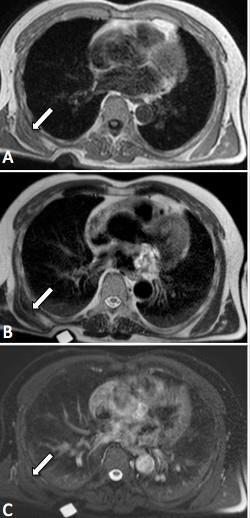

Esame mirato allo studio della tumefazione clinicamente apprezzabile in regione sottoscapolare dx. Reperti: a carico della regione dorsale profonda dx, tra la parete toracica post. ed il III° inf. della scapola, nello spazio delimitato anteriormente dal piano costale e post.te dai muscoli dentato ant. e lunghissimo del dorso, è presente una lesione delle parti molli a morfologia grossolanamente semilunare, delle dimensioni di circa mm 47AP x 13LL x 40CC. La concavità anteriore della semiluna appare a ridosso di due spazi intercostali e dell’elemento costale interposto. Tale lesione dai margini sfumati e maldelimitabili, presenta intensità di segnale simile a quella della muscolatura adiacente sia nelle sequenze T1- che T2-dipendenti, con qualche striatura interna compatibile con componente adiposa.

Dopo somministrazione e.v. di mdc, l’enhancement della lesione appare discreto e disomogeneo, progressivo, di tipo striato e con persistenza di accumulo nelle acquisizioni più tardive. Il

reperto non appare di sicura caratterizzazione potendo comunque essere riferito in prima ipotesi a formazione di derivazione fibroblastica/miofibroblastica a tipo “elastofibroma dorsi” (E.D.).

Si apprezza inoltre sottile impregnazione dopo mdc in sede analoga sin.; a tale livello tuttavia non si apprezzano attualmente aree con “effetto massa”. Quest’ultimo aspetto, nel sospetto di bilateralità della lesione, necessita di rivalutazione RM a distanza.

Il quadro RM tipico è quello di una lesione delle parti molli a morfologia grossolanamente semilunare con convessità rivolta verso la parte esterna della parete toracica. La lesione presenta margini sfumati e maldelimitabili ed intensità di segnale simile a quella della muscolatura adiacente sia nelle sequenze T1- che T2-dipendenti, con qualche striatura interna da componente adiposa (Fig. 1).

Dopo somministrazione ev di mdc, l’enhancement della lesione appare discreto e disomogeneo, progressivo, di tipo  striato e con persistenza di accumulo nelle acquisizioni più tardive (Fig. 3).